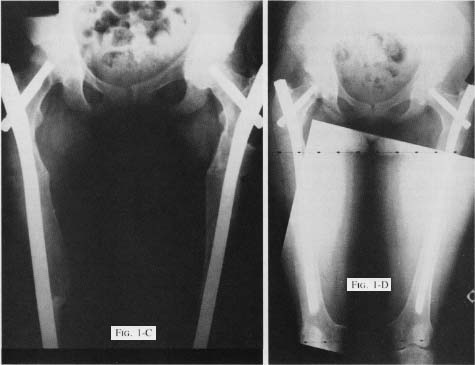

Fig 1C - Early postop healing at osteotomy sites. Fig 1D - 4 years postop.